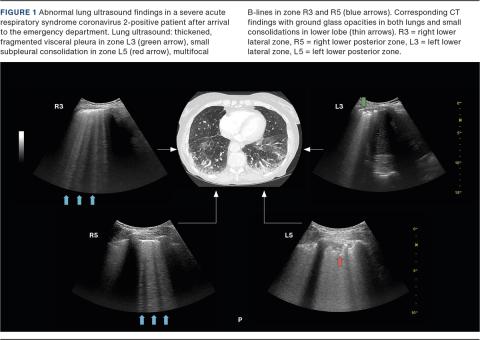

Of the 12 SARS-CoV-2-positive patients, 11 (92%) had an abnormal LUS, and four (33%) had one or more critical outcomes (Table 2). Specific LUS findings are presented in Table 2 and Figure 1. More than half of the COVID-19-infected patients had interstitial syndrome, multifocal small consolidations, pleural visceral thickening or a fragmented pleura line. All four COVID-19-infected patients admitted to the ICU had an abnormal LUS and interstitial syndrome at arrival.

LUS findings such as interstitial syndrome or focal B-lines, pleural thickening, multifocal small consolidations, fragmented pleural line and small pleural effusion seem to be common in COVID-19-infected patients and are highly consistent with CT findings [6, 16]. These findings were also present in this study, and most of them were significantly higher in SARS-CoV-2-positive patients (Table 2 and Figure 1). During the 14-day follow-up, no COVID-19-positive patients died, whereas two COVID-19-negative patients died. Both were older, with multiple co-morbidities and a no-resuscitation order.